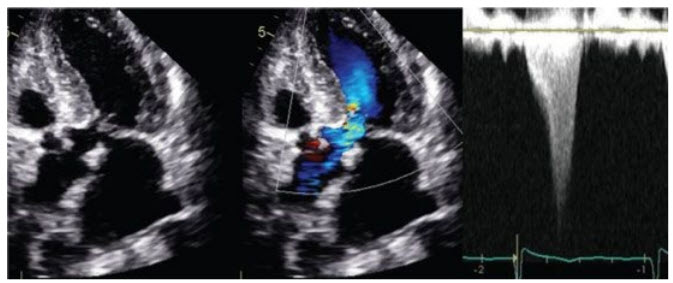

A 70-year-old man presents to your office with complaints of exertional dyspnea. He is mildly hypertensive on examination. Carotid upstrokes are brisk, with a secondary upstroke. A loud III/VI systolic murmur is heard along the sternal border radiating to the neck. S1 and S2 are normal. An S4 is heard. The murmur increases in intensity with Valsalva and decreases with handgrip.

An echocardiogram reveals a <2-m/s jet across the LVOT.

Repeat the echocardiogram with amyl nitrate (Fig. below). The physical examination is highly suggestive of hypertrophic cardiomyopathy (brisk, bisferiens carotid pulse, normal S2 , and murmur increasing with Valsalva and decreasing with handgrip). The patient may not have a significant resting gradient, but may have a significant provocable gradient. Generally, a transesophageal echocardiogram is not needed to make the diagnosis. Invasive hemodynamics with provocation would be useful, but angiography alone would not be sufficient.